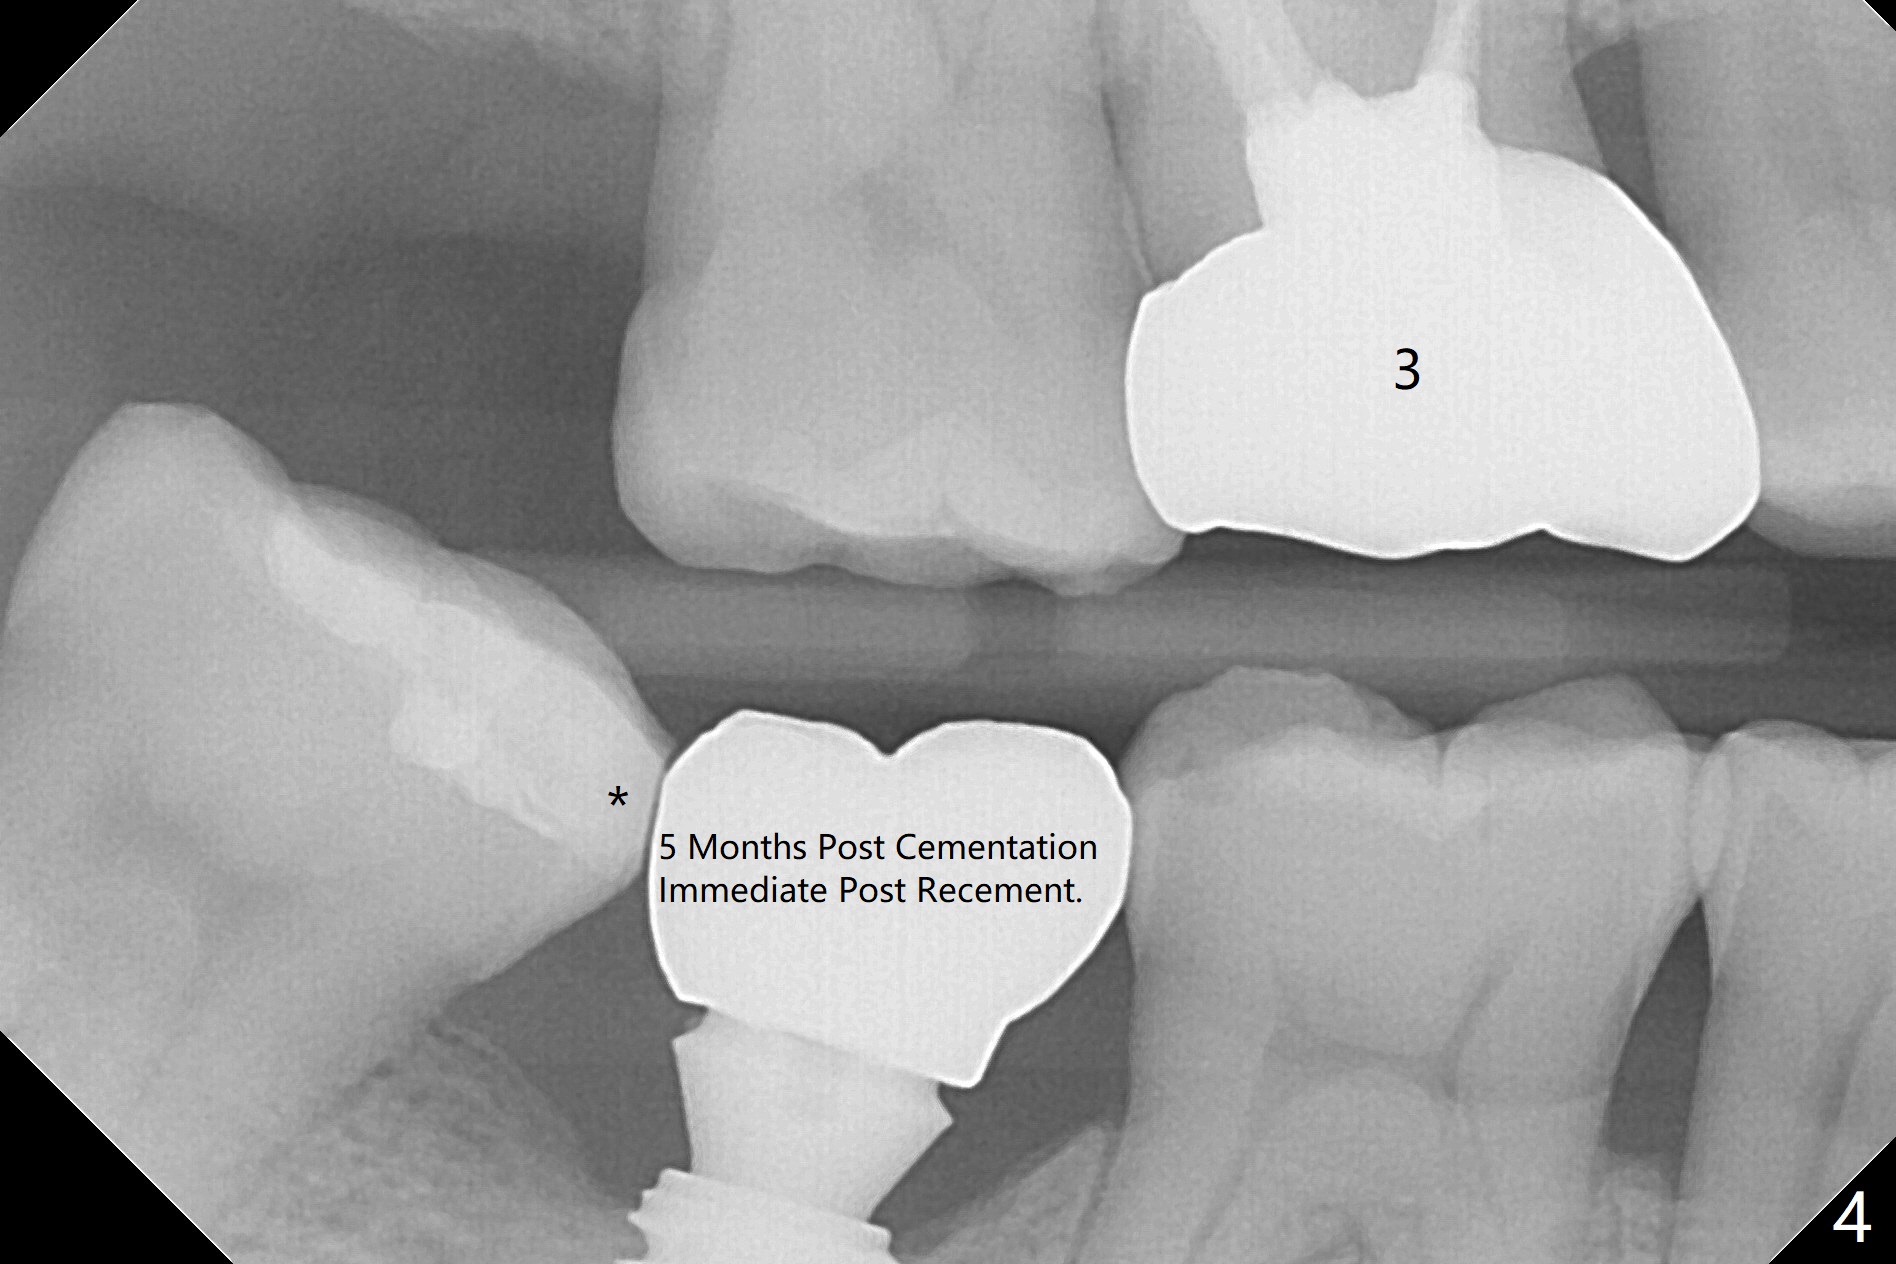

In fact 5x10 mm implant placement with guide requires using 5 mm cortical tap (Fig.1). When a 6x4 mm healing abutment is placed slightly supragingival, the clearance with the opposing supraerupted tooth is ~ 2 mm. It suggests that orthodontic intrusion is required for restoration. In fact the patient is incompliant with orthodontic mini-implant placement and retraction. When the implant at #31 is osteointegrated 4.5 months postop (Fig.2), it is used an anchor with an abutment and a provisional to intrude the opposing tooth. The final crown is cemented 10 months postop (Fig.3) with occlusal clearance (Fig.3' *). The contacts between #2 and 3 and between #31 and 32 are loose with papillary inflammation 5 months post cementation. It is planned to remove #31 crown/abutment for pick up impression/porcelain addition. Instead the crown is removed. After removing #32 MO composite with minor 2nd caries, new composite is placed (Fig.4 *) while the crown is reseated. When the crown is recemented, bitewing shows open margin (Fig.4), but the contact is wide and tight. After occlusal adjustment, occlusal contact at #31 and 32 mesial is heavier than that at #30. #3 crown is recommended. The occlusal table difference betweeen the upper 1st and 2nd molar is ~ 2 mmm preop (Fig.4'), whereas the difference is ~ .6 mm postop (in combination of occlusal equilibrium and intrusion of the upper 2nd molar (Fig.4)). It seems that orthodontic intrusion is not efficient in a male with bruxism. There is mild lingual (L) and distal bone loss 1.5 years post cementation (Fig.5) when CT is taken for #3 immediate implant. Lower Molar Immediate Implant, Armaments Xin Wei, DDS, PhD, MS 1st edition 07/12/2018, last revision 11/28/2020